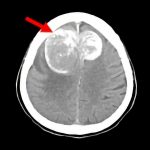

断層撮影